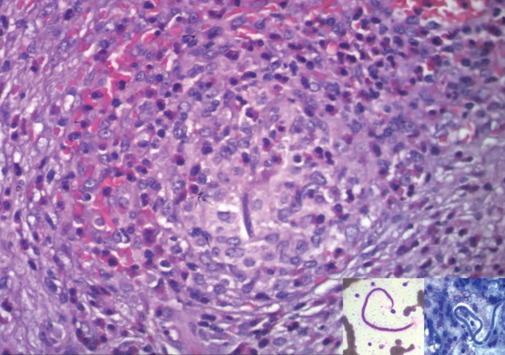

丝虫病是印度等热带和亚热带国家的主要公共卫生问题,其中90%的淋巴丝虫病是由班氏武契罗菲亚(Wuchereria bancrofti)引起的。由于免疫系统与微丝蚴及其扩散产物相互作用而引起的淋巴外表现很少见。在各种受累器官中,脾脏受累是丝虫病罕见的淋巴外表现,临床放射学上可表现为与已知恶性肿瘤相关的转移瘤或淋巴瘤等原发性恶性肿瘤。在此,我们介绍了一例不寻常的病例,患者为一名20岁女性,伴有外周血嗜酸性粒细胞增多,同时患有脾丝虫病和胰腺实性假乳头状上皮肿瘤。

Filariasis is a major public health concern in tropical and subtropical countries like India with Wuchereria bancrofti accounting for 90% of lymphatic filariasis. Rarely observed are extra lymphatic manifestations caused by interaction of immune system with microfilaria and their diffusible products. Among various organs involved, splenic involvement is a rare extra lymphatic manifestation of filariasis and can masquerade clinicoradiologically as metastasis when associated with a known malignancy or as a primary malignancy like lymphoma. Hereby, we present an unusual case of coincidence of splenic filariasis with pancreatic solid pseudopapillary epithelial neoplasm in a 20-year-old woman associated with peripheral blood eosinophilia.